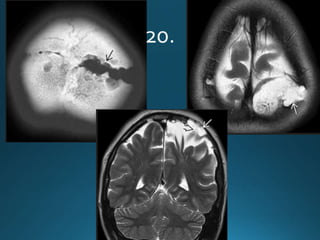

Giant cerebral aneurysms are ones that measure >25 mm in

greatest dimension.

Clinical presentation

Patients can present with symptoms and signs of mass effect

or subarachnoid haemorrhage 1,2.

Most commonly represent saccular cerebral aneurysms but

may also be fusiform or serpentine in morphology .They are

thought to develop via two pathways :

• internal elastic lamina de novo defect

• enlargement from a smaller aneurysm

MRI

On MRI also the patent and thrombosed aneurysm display different imaging

features:

T1

most of the patent aneurysm appears as flow void, or they may show

heterogeneous signal intensity

in thrombosed aneurysm appearance depends on the age of clot within the

lumen

T2

typically hypointense

laminated thrombus may show a hyperintense rim